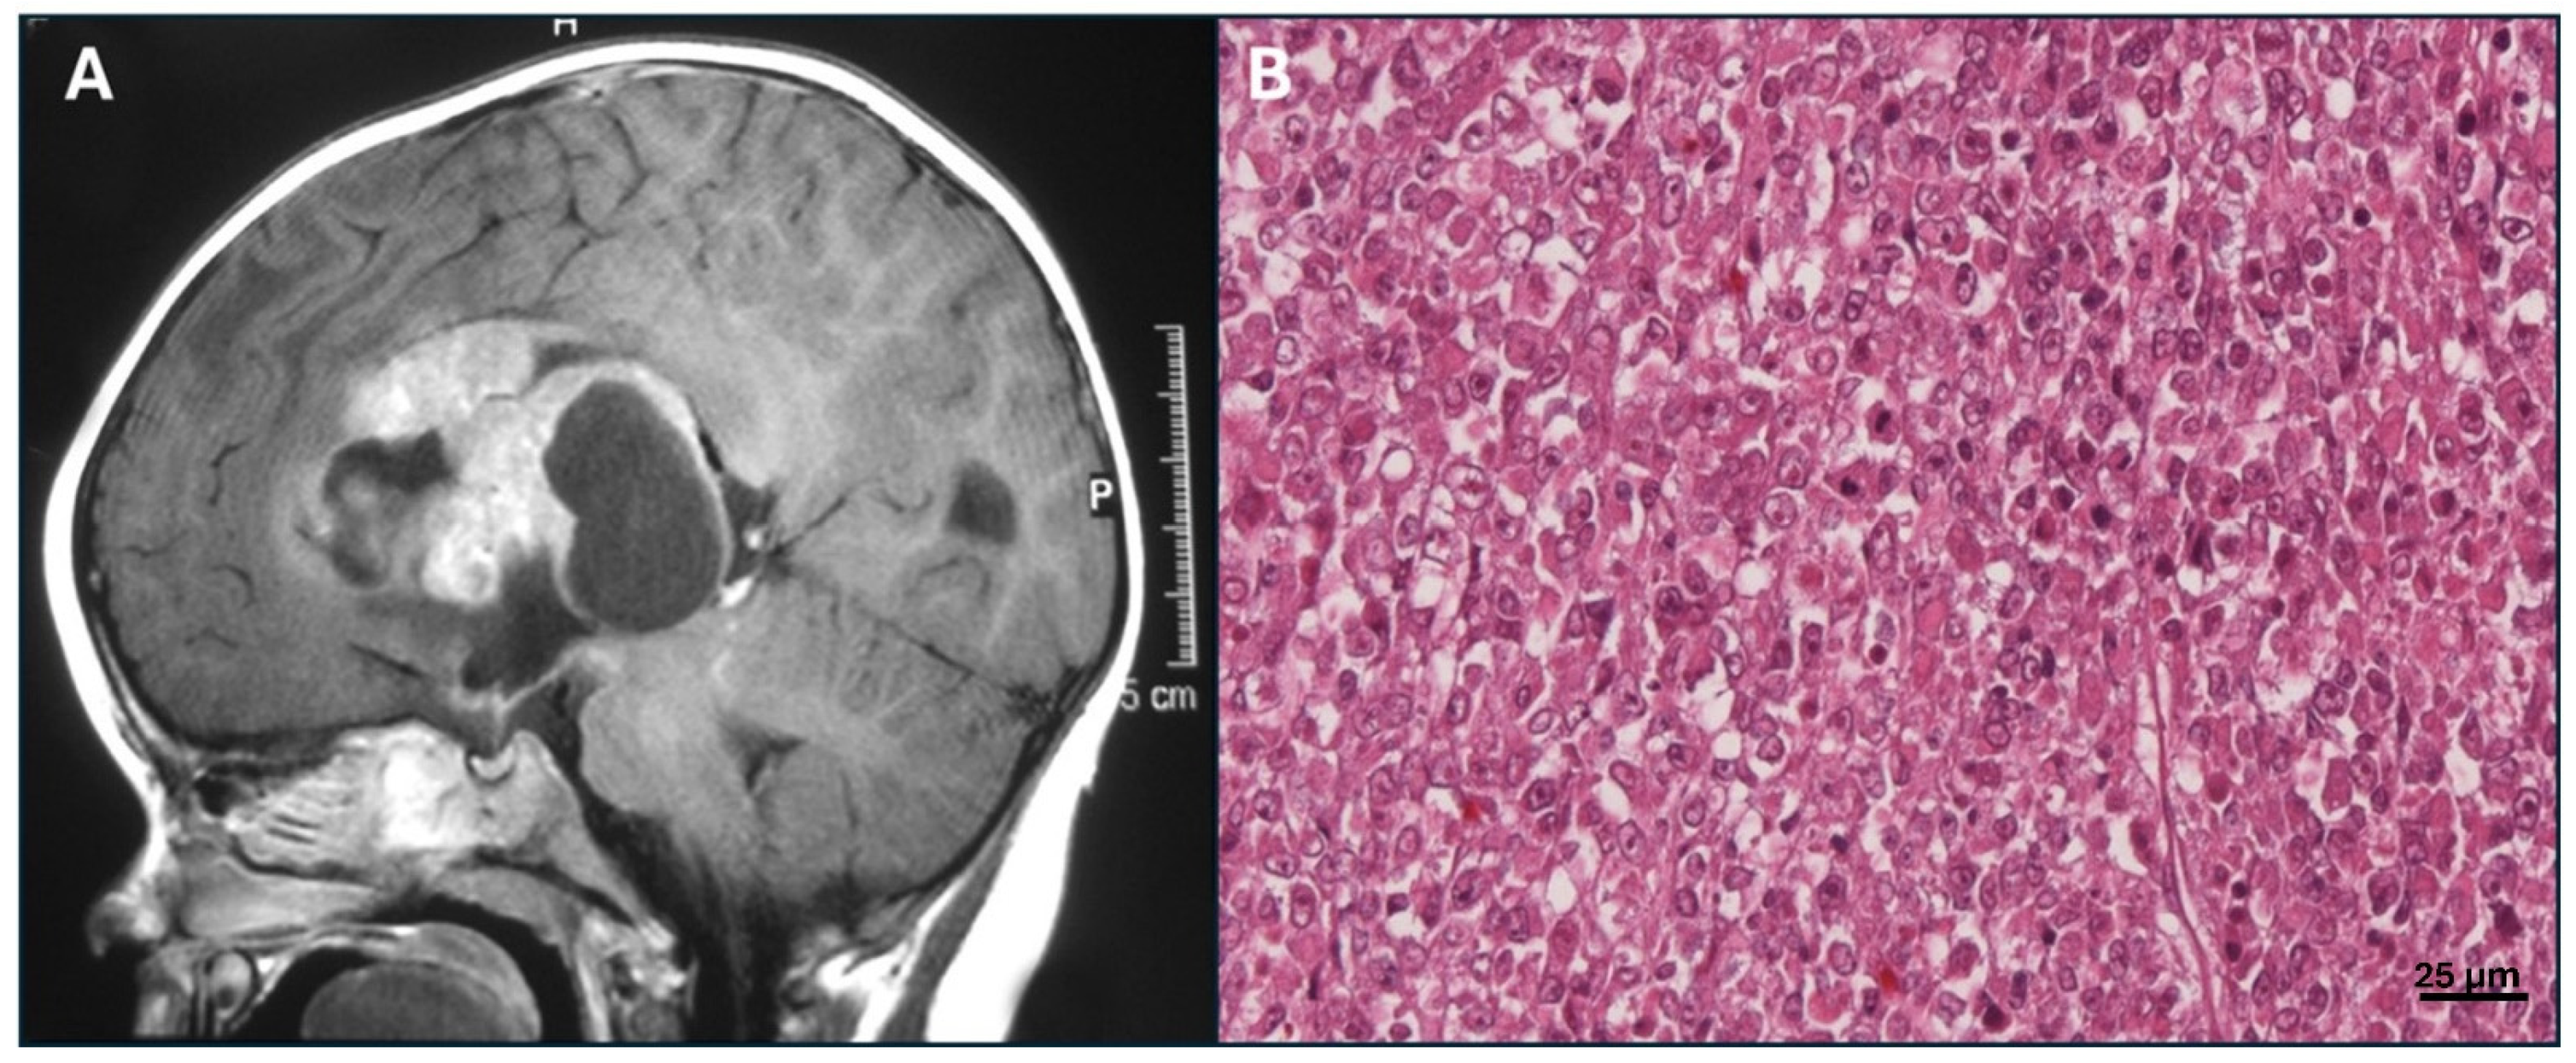

- Thomas, C.; Oehl-Huber, K.; Bens, S.; Soschinski, P.; Koch, A.; Nemes, K.; Oyen, F.; Kordes, U.; Kool, M.; Frühwald, M.C.; et al. Transposable Element Insertion as a Mechanism of SMARCB1 Inactivation in Atypical Teratoid/Rhabdoid Tumor. Genes. Chromosomes Cancer 2021, 60, 586–590. [Google Scholar] [CrossRef]

- Frühwald, M.C.; Biegel, J.A.; Bourdeaut, F.; Roberts, C.W.M.; Chi, S.N. Atypical Teratoid/Rhabdoid Tumors-Current Concepts, Advances in Biology, and Potential Future Therapies. Neuro-Oncol. 2016, 18, 764–778. [Google Scholar] [CrossRef] [PubMed]

- Slavc, I.; Chocholous, M.; Leiss, U.; Haberler, C.; Peyrl, A.; Azizi, A.A.; Dieckmann, K.; Woehrer, A.; Peters, C.; Widhalm, G.; et al. Atypical Teratoid Rhabdoid Tumor: Improved Long-Term Survival with an Intensive Multimodal Therapy and Delayed Radiotherapy. The Medical University of Vienna Experience 1992–2012. Cancer Med. 2014, 3, 91–100. [Google Scholar] [CrossRef] [PubMed]

- Ho, B.; Johann, P.D.; Grabovska, Y.; De Dieu Andrianteranagna, M.J.; Yao, F.; Frühwald, M.; Hasselblatt, M.; Bourdeaut, F.; Williamson, D.; Huang, A.; et al. Molecular Subgrouping of Atypical Teratoid/Rhabdoid Tumors-a Reinvestigation and Current Consensus. Neuro-Oncol. 2020, 22, 613–624. [Google Scholar] [CrossRef] [PubMed]

- Reddy, A.T.; Strother, D.R.; Judkins, A.R.; Burger, P.C.; Pollack, I.F.; Krailo, M.D.; Buxton, A.B.; Williams-Hughes, C.; Fouladi, M.; Mahajan, A.; et al. Efficacy of High-Dose Chemotherapy and Three-Dimensional Conformal Radiation for Atypical Teratoid/Rhabdoid Tumor: A Report From the Children’s Oncology Group Trial ACNS0333. J. Clin. Oncol. Off. J. Am. Soc. Clin. Oncol. 2020, 38, 1175–1185. [Google Scholar] [CrossRef]